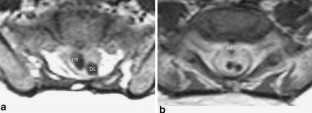

Cases of infected dermal sinus are scarce and detailed surgical anatomical descriptions are hardly found in literature. The clinical, radiological, and surgical findings in four cases of an infected dermal sinus located at the lower spine are presented to elucidate the pathological anatomical configuration.

The first case showed two dermal sinuses with a parallel course extra- and intradurally, ending in a confluence of cavities connected to the conus. In this case, as well as in the fourth case, the signs and symptoms were those of meningitis. The second case presented with meningitis and a subdural empyema, while the third case presented with an intradermoid–intramedullary abscess at the junction between the DS and the conus. This child probably showed signs and symptoms of conus involvement as early as during pregnancy.

The anatomy of the nervous elements in this congenital anomaly is heavily disturbed, more particularly in case of infection, due to extensive arachnoidal scarring. The latter renders dissection laborious and recognition of anatomical details difficult, resulting in complete excision of a dermal sinus in less than half of the cases. Despite their variability in presentation, most cases of an infected dermal sinus show similar characteristic features.